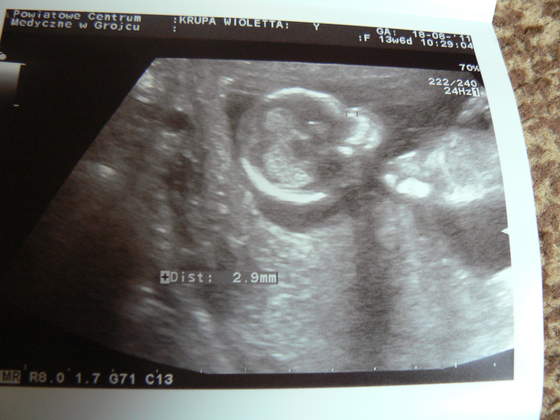

Ale najważniejsze: kość nosowa w porządku: 2,9mm, a przezierność karkowa: 1,1mm, czyli wszystko jak najbardziej w porządku!!!

A oto moje maleństwo:

Zobacz załącznik 382631Zobacz załącznik 382632Zobacz załącznik 382633